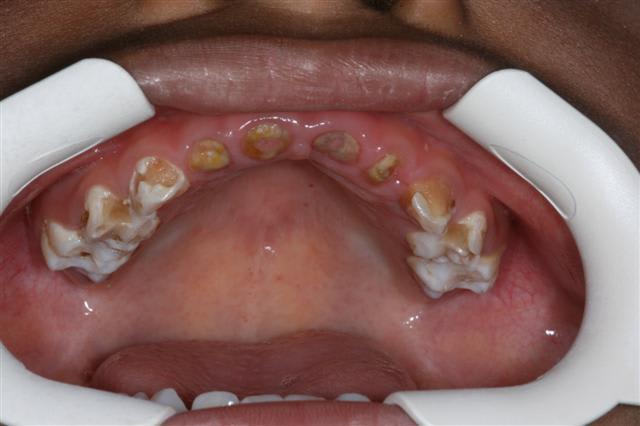

antoine 4 ans1/2

vu en Mars 2007 :traitement 55 -85-51-61

et commencé

- couronnes pedo(54-64-65-75) sur dts vivantes: trop délabrées pr pouvoir reconstituer correctement en retrouvant une DV correcte mais de la dentine réactionnelle,pas d'infection

-compos sur 53 et 63

-les anterieures je ne sais pas encore...